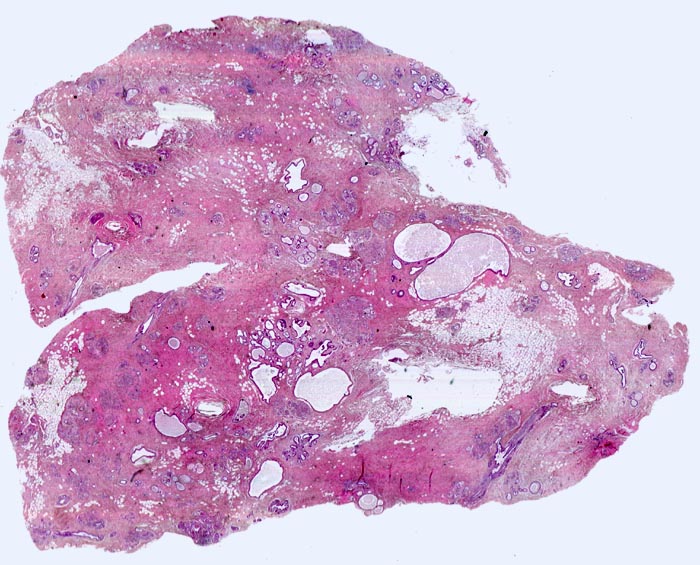

fibrös zystische Mastopathie mit Mikroverkalkungen

Ausgedehnte Fibroseareale schliessen kleine Inseln von Fettgewebe ein. Zahlreiche Gänge sind unterschiedlich stark dilatiert. Zusammen ergibt sich die Diagnose einer fibrös zystischen Mastopathie.

Probeexzision wegen umschriebenen Mikroverkalkungen in der Screeningmammographie. Bei der Palpation lassen sich mehrere unscharf begrenzte derbe Knoten tasten.